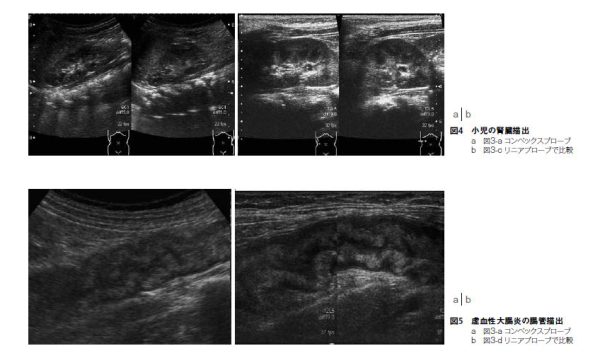

3. リニアプローブ PLT-704SBT( 中心7.5MHz 視野幅約38mm)(図3-c)

消化管検査、小児の腎臓、胆道系の描出にも用いる(図4)。

4. リニアプローブ PLT-1005BT(中心10.0MHz 視野幅約58mm)(図3-d)

消化管検査(特に消化管の壁辺縁や周囲リンパ節の描出)などにも用いる(図5)。